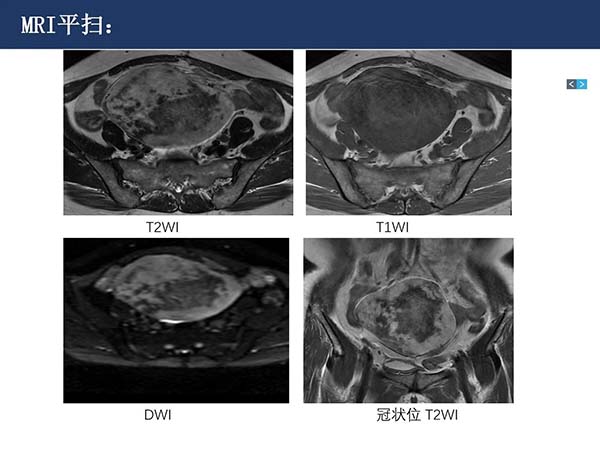

【杨柳病例】腹盆腔韧带样纤维瘤病